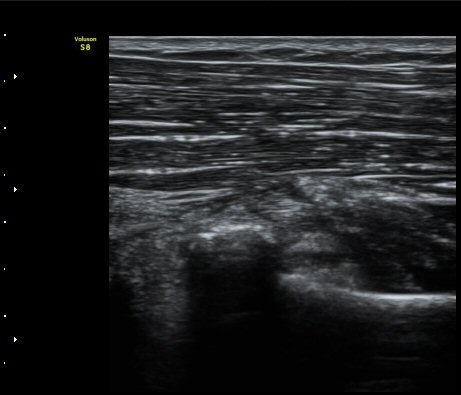

¿ä°ñµÎ Ⱦ´Ü¸é°Ë»ç¿¡¼­ ƯÀÌ ¼Ò°ßÀ» º¸ÀÌÁö ¾ÊÀ½(±×¸² 4)